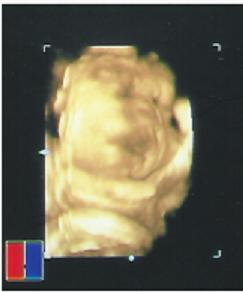

検診に行ってきました。 グーちゃんは30週目。 診察室に入るなり、先生が...